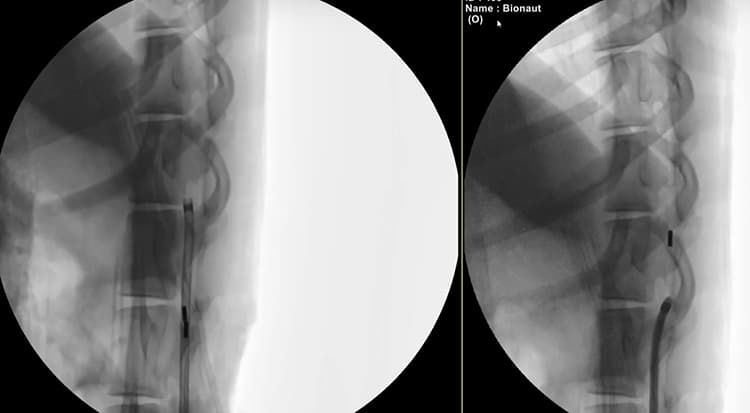

Measuring less than one millimeter in length, the 3D-printed Bionauts contain moving parts controlled remotely by a magnetic guidance system. The magnetic energy required to operate the robot is less than 10% of that used in MRIs and is much cheaper to generate, according to Diamandis. These miniature medical machines are actually capable of autonomous operation but humans will remain in the loop, especially in the early days.

The bot is injected either into the lumbar spine, like in an epidural procedure, or behind the skull. It then speeds and slices its way through tissue to the target site, such as a tumor, where it is magnetically triggered to release a drug payload from the cargo compartment. The robot then returns the way it came. Bionauts can even go “off road” compared to conventional technologies that stick to established routes such as the vasculature. For example, they can swim through cerebrospinal fluid or even burrow through brain tissue. The accuracy is on par with surgeons, with a deviation of just one millimeter. The robot can be designed in a range of sizes, payloads, shapes, topologies, functions, and flavors. We might have made up one of those.